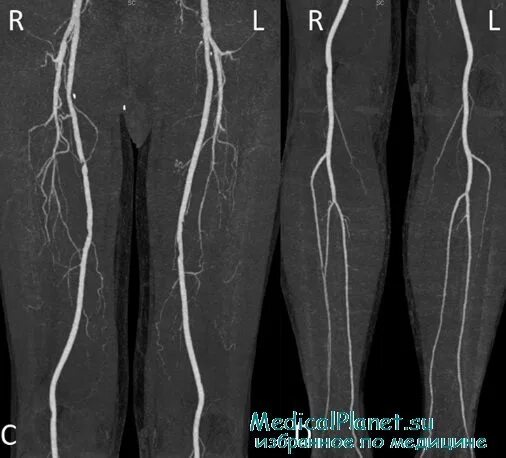

Атеросклероз артерий нижних конечностей ангиография. атеросклероз нижних конечностей кт. флебография вен нижних конечностей варикоз. атеросклероз артерий нижних конечностей на кт.

Облитерирующий атеросклероз артерий нижних конечностей. атеросклероз сосудов нижних конечностей. стеноз артерий нижних конечностей.

Мскт флебография вен нижних конечностей. магнитно-резонансная ангиография сосудов нижних конечностей. мра (магнитно-резонансная ангиография). кт флебография вен нижних конечностей.

Облитерирующий атеросклероз артерий нижних конечностей. облитерирующий атеросклероз сосудов конечностей. атеросклеротические поражения периферических сосудов. атеросклероза (облитерирующего) артерий ног.